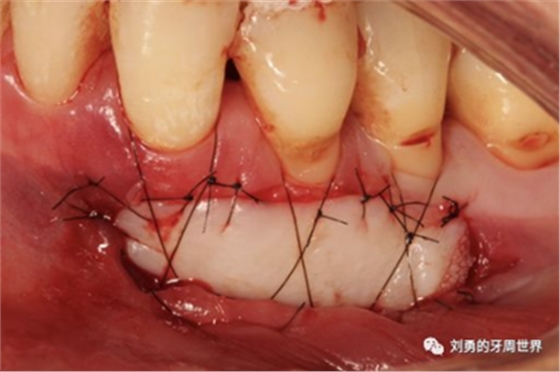

該方式齦瓣固定的效果差,術后血供差,為了改善血供,我們提倡下面的改良縫合方式,血供更好,成功率更高,如下圖:

通過用縫線壓迫的方式固定,術后愈合的過程齦瓣始終與受區(qū)骨膜貼合,而不會移動。